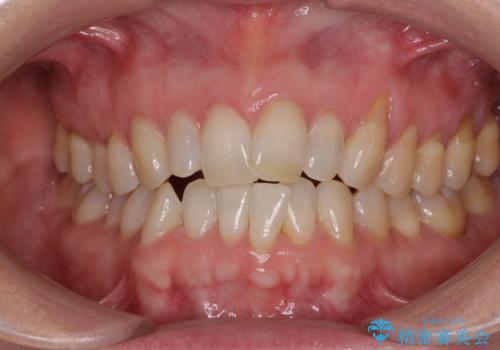

- 前歯の上下スペースによる食べにくさを気にして来院された患者様です。

インビザラインにより上下の前歯の隙間を閉じていくこととしました。

舌の突出癖があると上下前歯にスペースが開くため、矯正治療を機会に舌癖を改善するトレーニングを行ってもらい、矯正治療後の後戻りを防止するように指導しています。